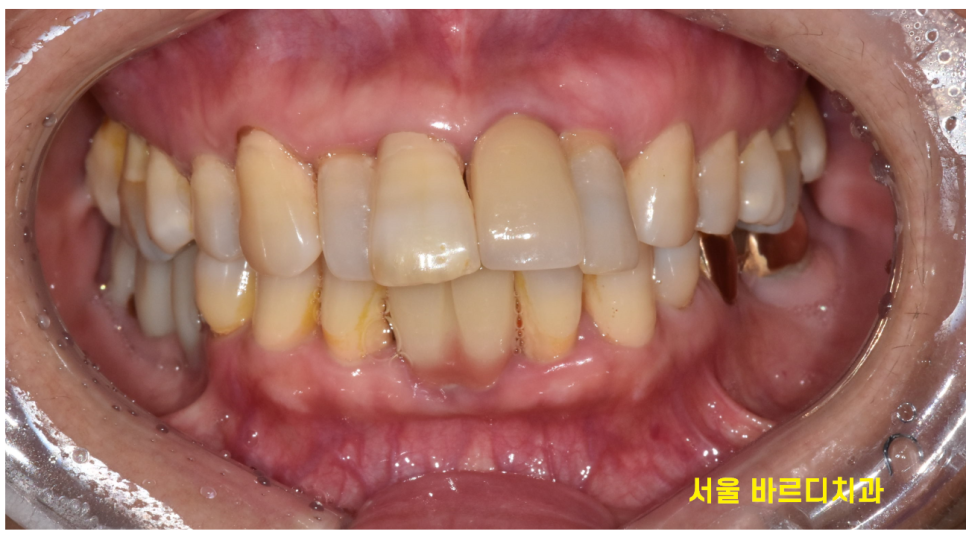

윗니 흔들림으로 방문해주신 환자분입니다.

환자분은 잇몸이 약해서 계속해서 하나씩 치료를 하고 계셨다했는데요.

앞니에 임플란트 한 것도 보이고

보철로 씌운것도 있더라고요~

이 글을 보시는 환자분들은 사진만 봐서는

잘 모르시겠지만

전문가의 보철한 부분이 눈으로는 다 보입니다 ㅎㅎ